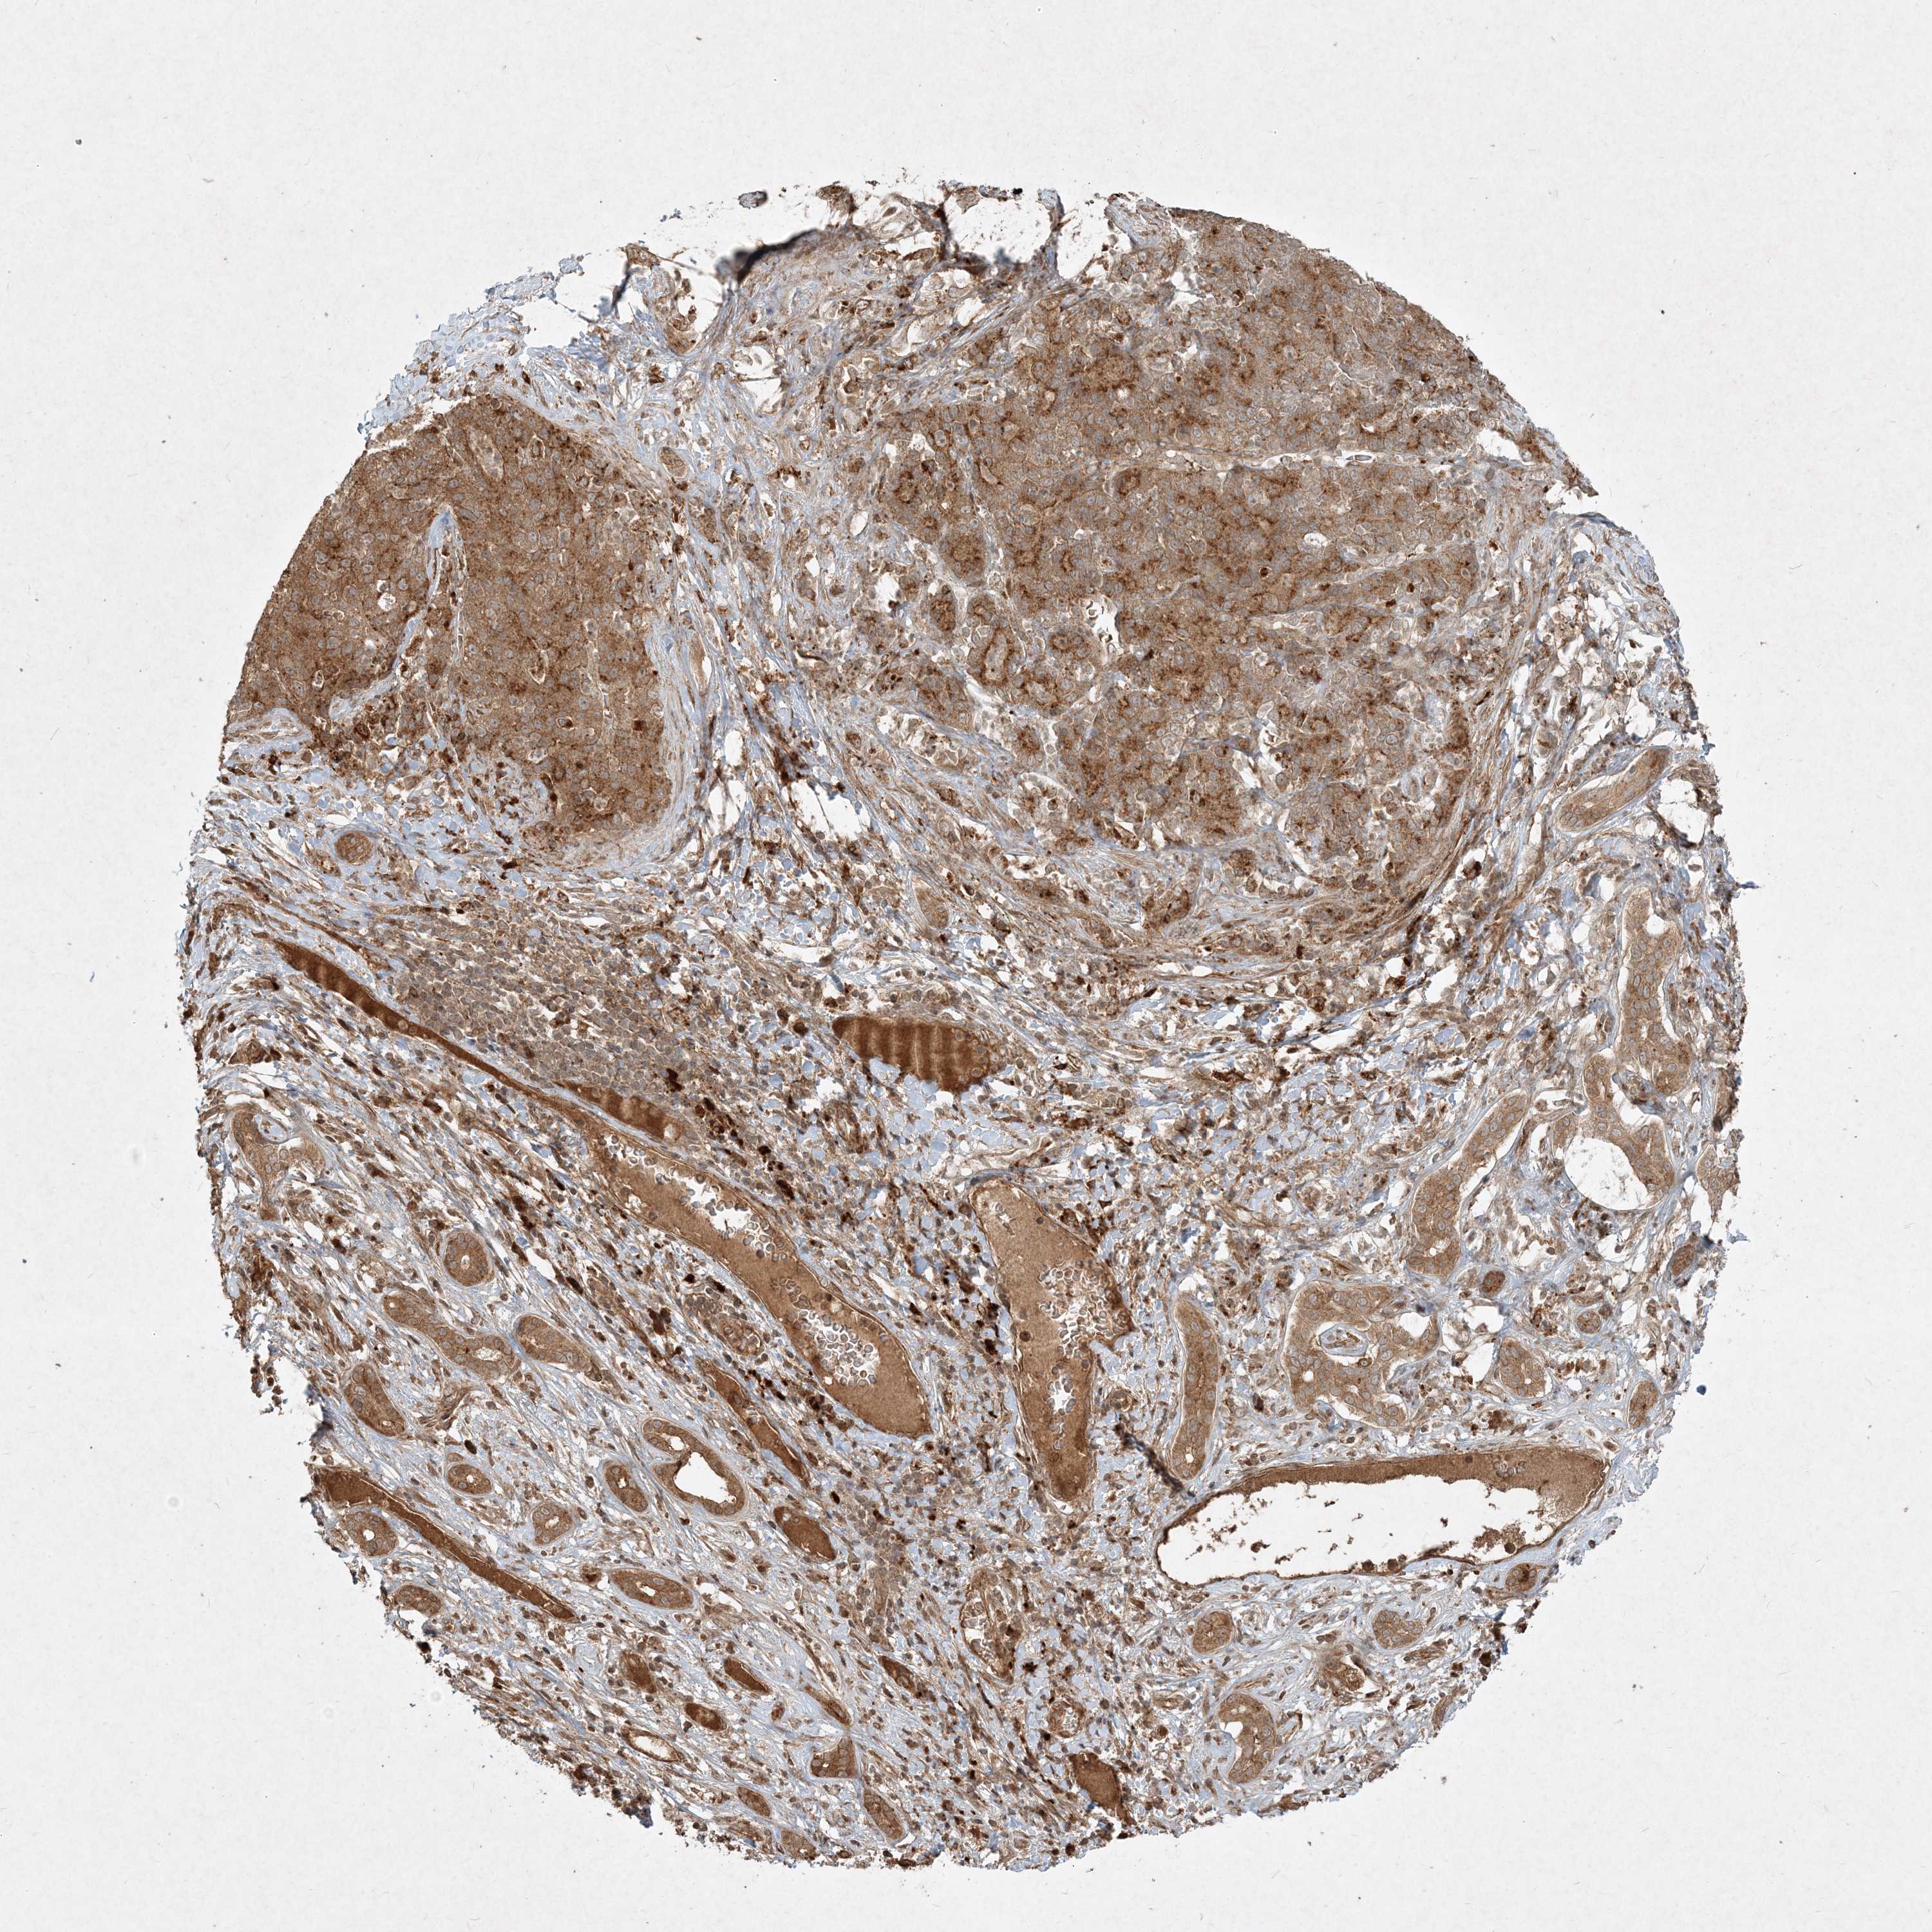

LIVER CANCER - Protein expressioni

A mouse-over function shows sample information and annotation data. Click on an image to view it in a full screen mode. Samples can be filtered based on level of antibody staining by selecting one or several of the following categories: high, medium, low and not detected. The assay and annotation is described here.

Note that samples used for immunohistochemistry by the Human Protein Atlas do not correspond to samples in the TCGA dataset.

Antibody stainingi

Antibody staining in the annotated cell types in the current human tissue is reported as not detected, low, medium, or high, based on conventional immunohistochemistry profiling in selected tissues. This score is based on the combination of the staining intensity and fraction of stained cells.

Each image is clickable and will lead to virtual microscopy that enables deeper exploration of all samples and also displays staining intensity scores, fraction scores and subcellular localization as well as patient and tissue information for each sample.

Antibody HPA040017

Antibody CAB034257

Staining

High

Medium

Low

Not detected

Intensity

Strong

Moderate

Weak

Negative

Quantity

>75%

75%-25%

<25%

None

Location

Nuclear

Cytoplasmic/membranous

Cytoplasmic/membranous,nuclear

Cholangiocarcinoma

Carcinoma, Hepatocellular, NOS